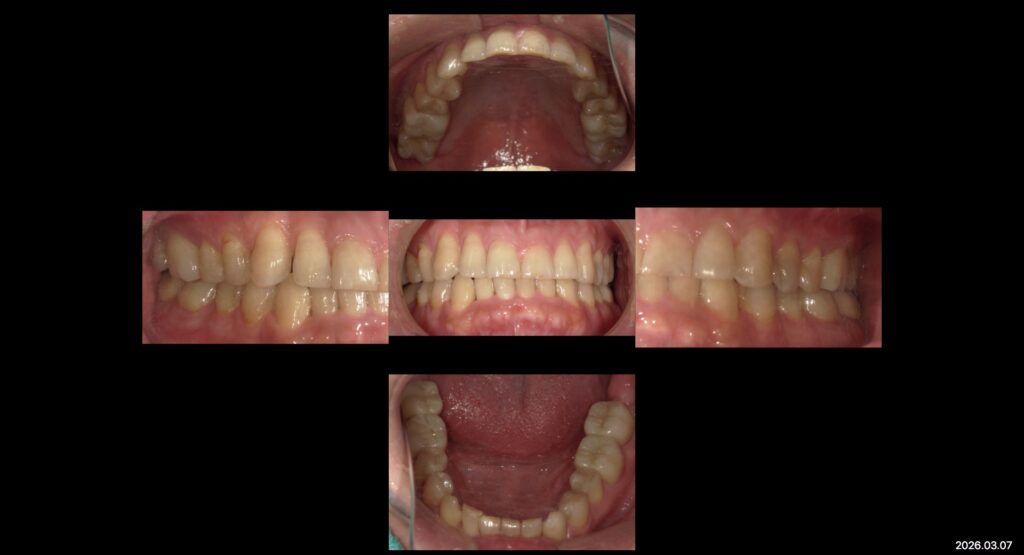

症例ー全顎治療ー

上:初診時口腔内写真

下:補綴治療後口腔内写真

本日は補綴治療を終えた患者様の症例写真です

前歯の歯並びと、噛み合わせの改善・予防治療を目的に奥歯の補綴治療を行いました。

現在はメンテナンスに通っていただきながら経過観察を追っております。